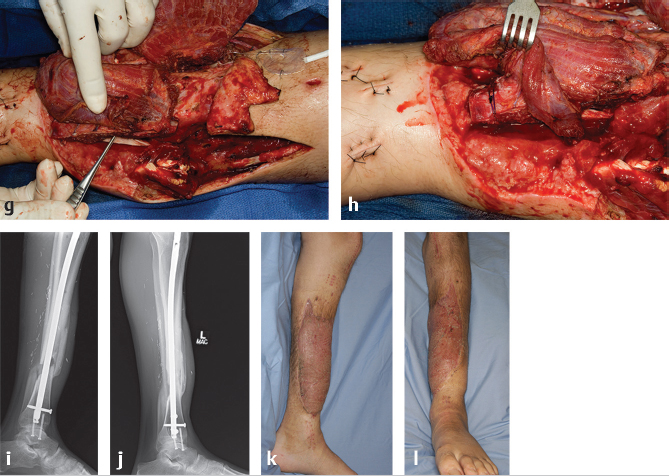

Fig. 23.2 (a) Anteroposterior radiograph of a 28-year-old man who suffered an open compound fracture of his tibia and fibula. (b) Reconstruction is started with debridement of the bone defect and (c) extensive debridement of the surrounding dead muscle and soft tissue. (d) A single rib is harvested with the serratus and latissimus for soft-tissue coverage and bony reconstruction. (e) This intraoperative image shows the vessel loops surrounding branches of thoracodorsal vessels. The arrowhead points to the rib and the arrow points to the pleura. The chest defect can be covered with synthetic mesh or acellular dermal matrix. (f) The chimeric flap is transferred to the leg where an end-to-side anastomosis is performed between the thoracodorsal artery and the posterior tibial artery. The long pedicle length allows for easy insetting of the rib. (g) The rib is secured to the tibia with sutures placed (h) through bone tunnels. The fracture is also stabilized with an intramedullary rod. (i) Postoperative radiograph at 5 months showing early consolidation and at 2 years (j) showing bony union with hypertrophy of rib graft. (k, l) Clinical appearance of the leg at 5 months postoperatively.